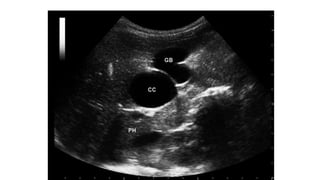

USG

• Ballooned/fusiform cyst beneath porta hepatis separate from GB

• *Communication with bile duct needs to be demonstrated*

• Abrupt change of caliber at junction of dilated segment to normal

ducts

• Intrahepatic bile duct dilatation secondary to stenosis.

USG • Ballooned/fusiform cystbeneath porta hepatis separate from GB • *Communication with bile duct needs to be demonstrated* • Abrupt change of caliber at junction of dilated segment to normal ducts • Intrahepatic bile duct dilatation secondary to stenosis.